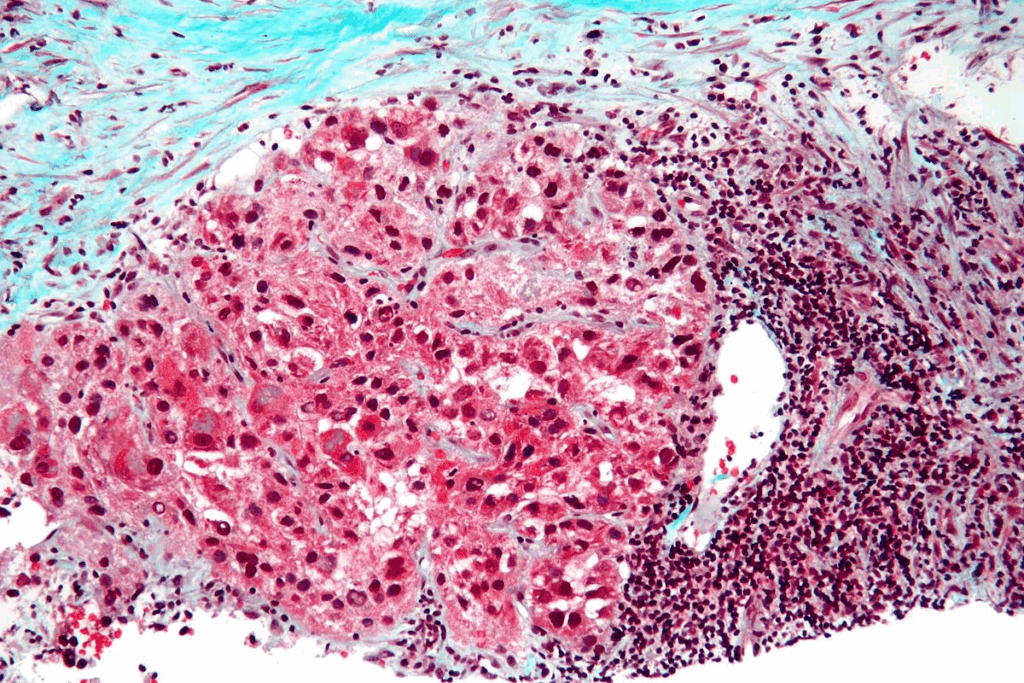

Diagnostic Criteria and Classification

To diagnose sarcoma botryoides, doctors use several methods. They look for grape-like clusters or polypoid masses. They also examine cells under a microscope. These cells are small and round or spindle-shaped, in a myxoid background.

Diagnostic FeatureDescription

Gross AppearanceGrape-like or polypoid masses

Histological CharacteristicsSmall, round, or spindle-shaped cells with a myxoid background

Common LocationsHollow organs like the bladder and vagina

Sarcoma botryoides is classified as a type of embryonal rhabdomyosarcoma. Knowing this helps doctors choose the right treatment and predict how well the patient will do.